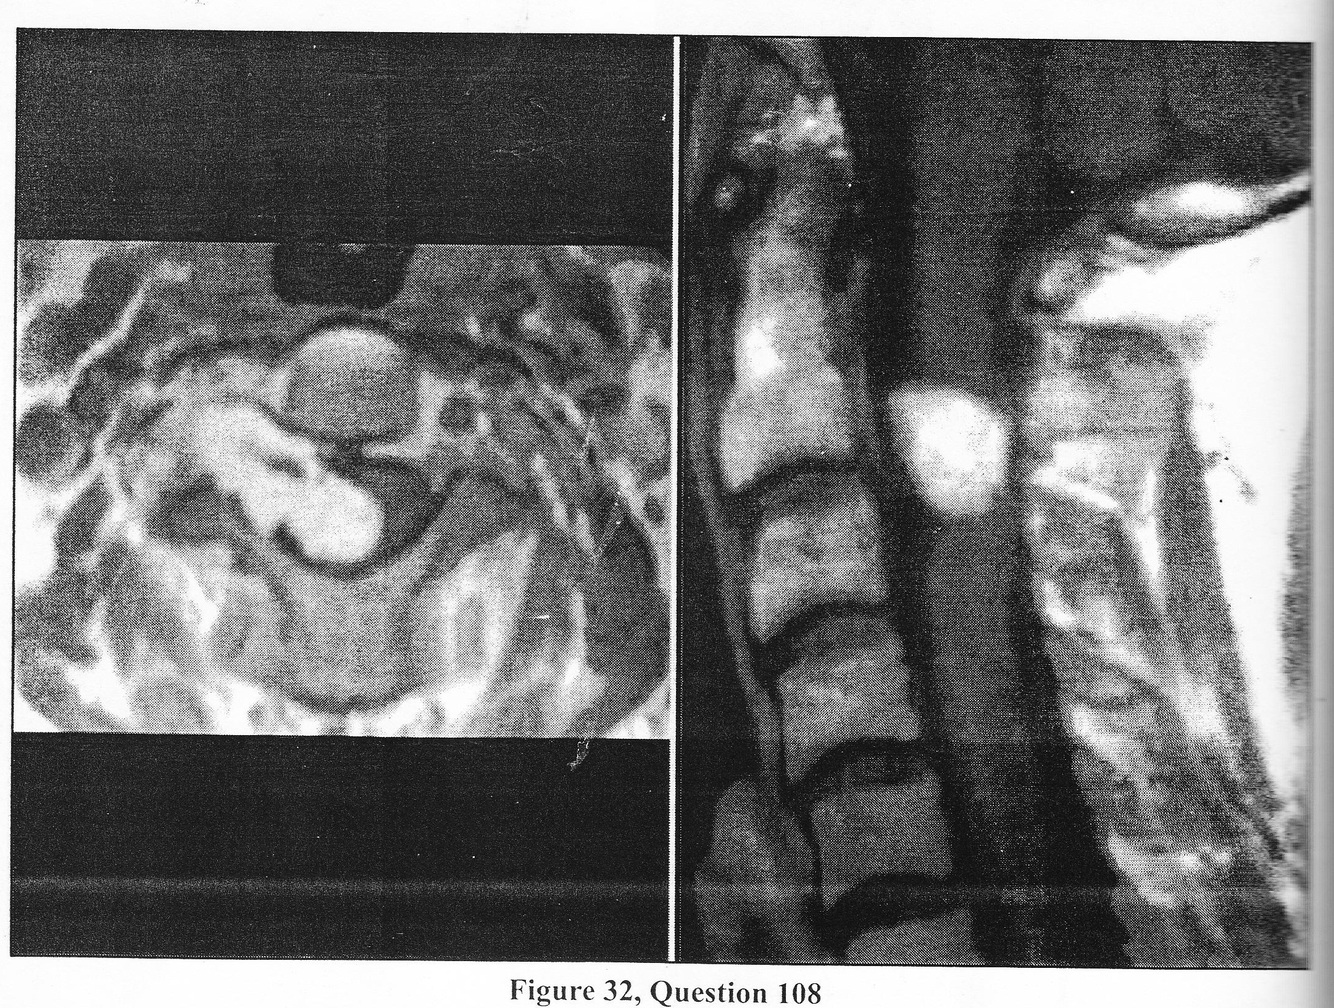

A. L4-5 central disc herniation wth compressin of both L5 nerve roots’

B. left L4-5 paracentral disc herniation with compression of L5 nerve root

C. left L5-S1 far lateral disc herniation with L5 nerve root compression

D. left L5-S1 paracentral disc herniation with S1 nerve root compression

E. left L4- S1 far lateral disc herniation with L4 nerve root compression